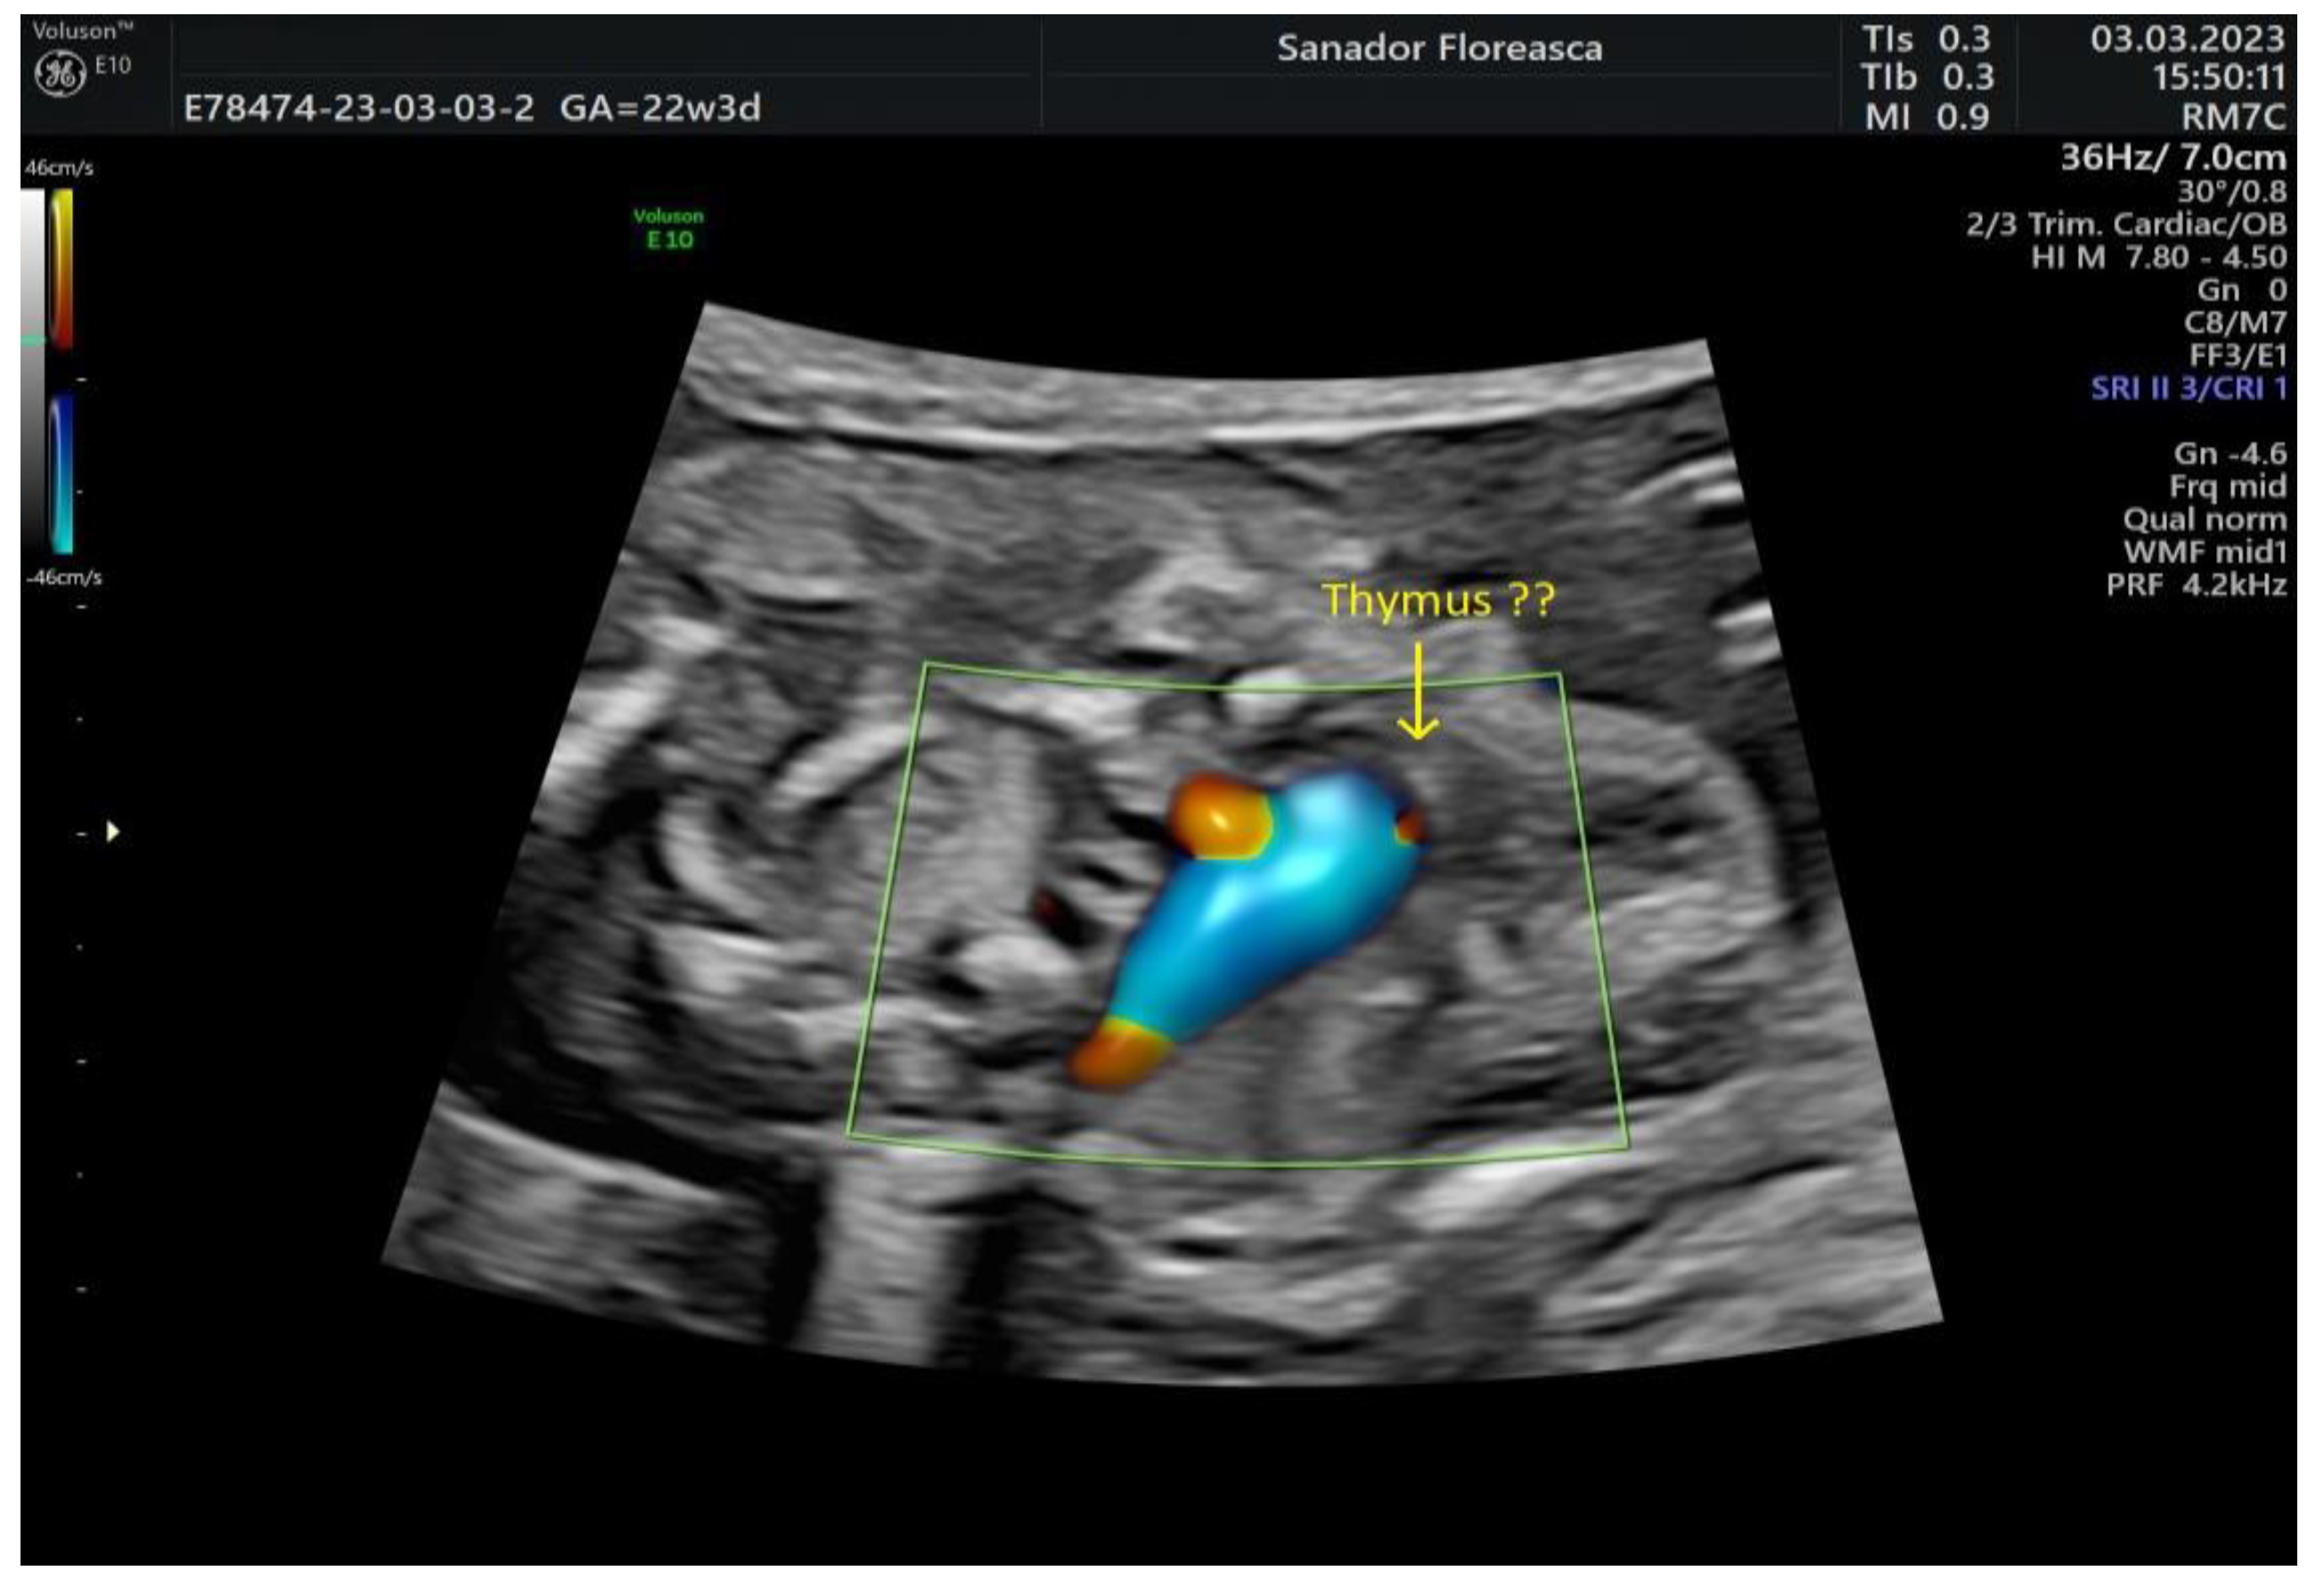

Other ultrasonographic findings | Polyhydramnios Enlarged CSP Thymus hypoplasia Bulbous nose |